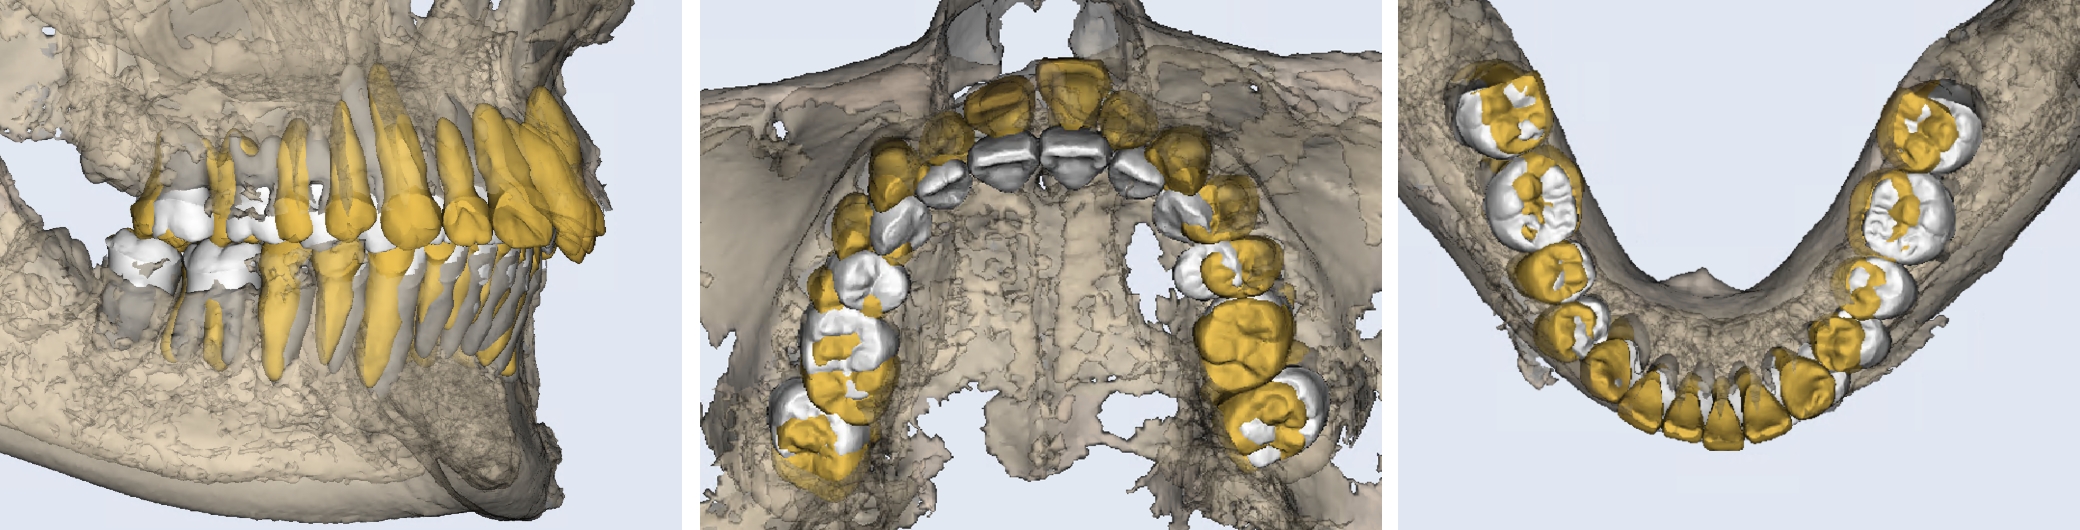

3Dセットアップで仕上がりを「見える化」

(成人矯正)

当院は自費の成人矯正の全症例で3Dセットアップを行います。

まず、セファロ・3DCT(あごの骨や歯の根の情報)・口腔内スキャン(歯の形とかみ合わせの情報)をとり、これらを重ね合わせて1本ずつ歯をデジタル上で並べ直すシミュレーションを作成します。

何がわかる・何が良い?

• 骨の中で無理のない位置に歯を動かせているかを事前に確認できる

• 歯ぐきの下がりや、骨から外れるなどのリスクを低減できる

• 見た目(口元のバランス)と噛む機能を両立した、現実的で長期安定しやすいゴールを設定できる

• 移動できる範囲(安全域=歯槽骨の包絡)を把握し、過度な移動を避ける設計ができる

3DCTの治療例

初診とセットアップ重ね合わせ

セットアップと終了時重ね合わせ

治療が終わる頃の歯の位置は、事前に作成した3Dセットアップで想定した「骨の中で無理のない位置」とほぼ一致しています。※症例により個人差があります。